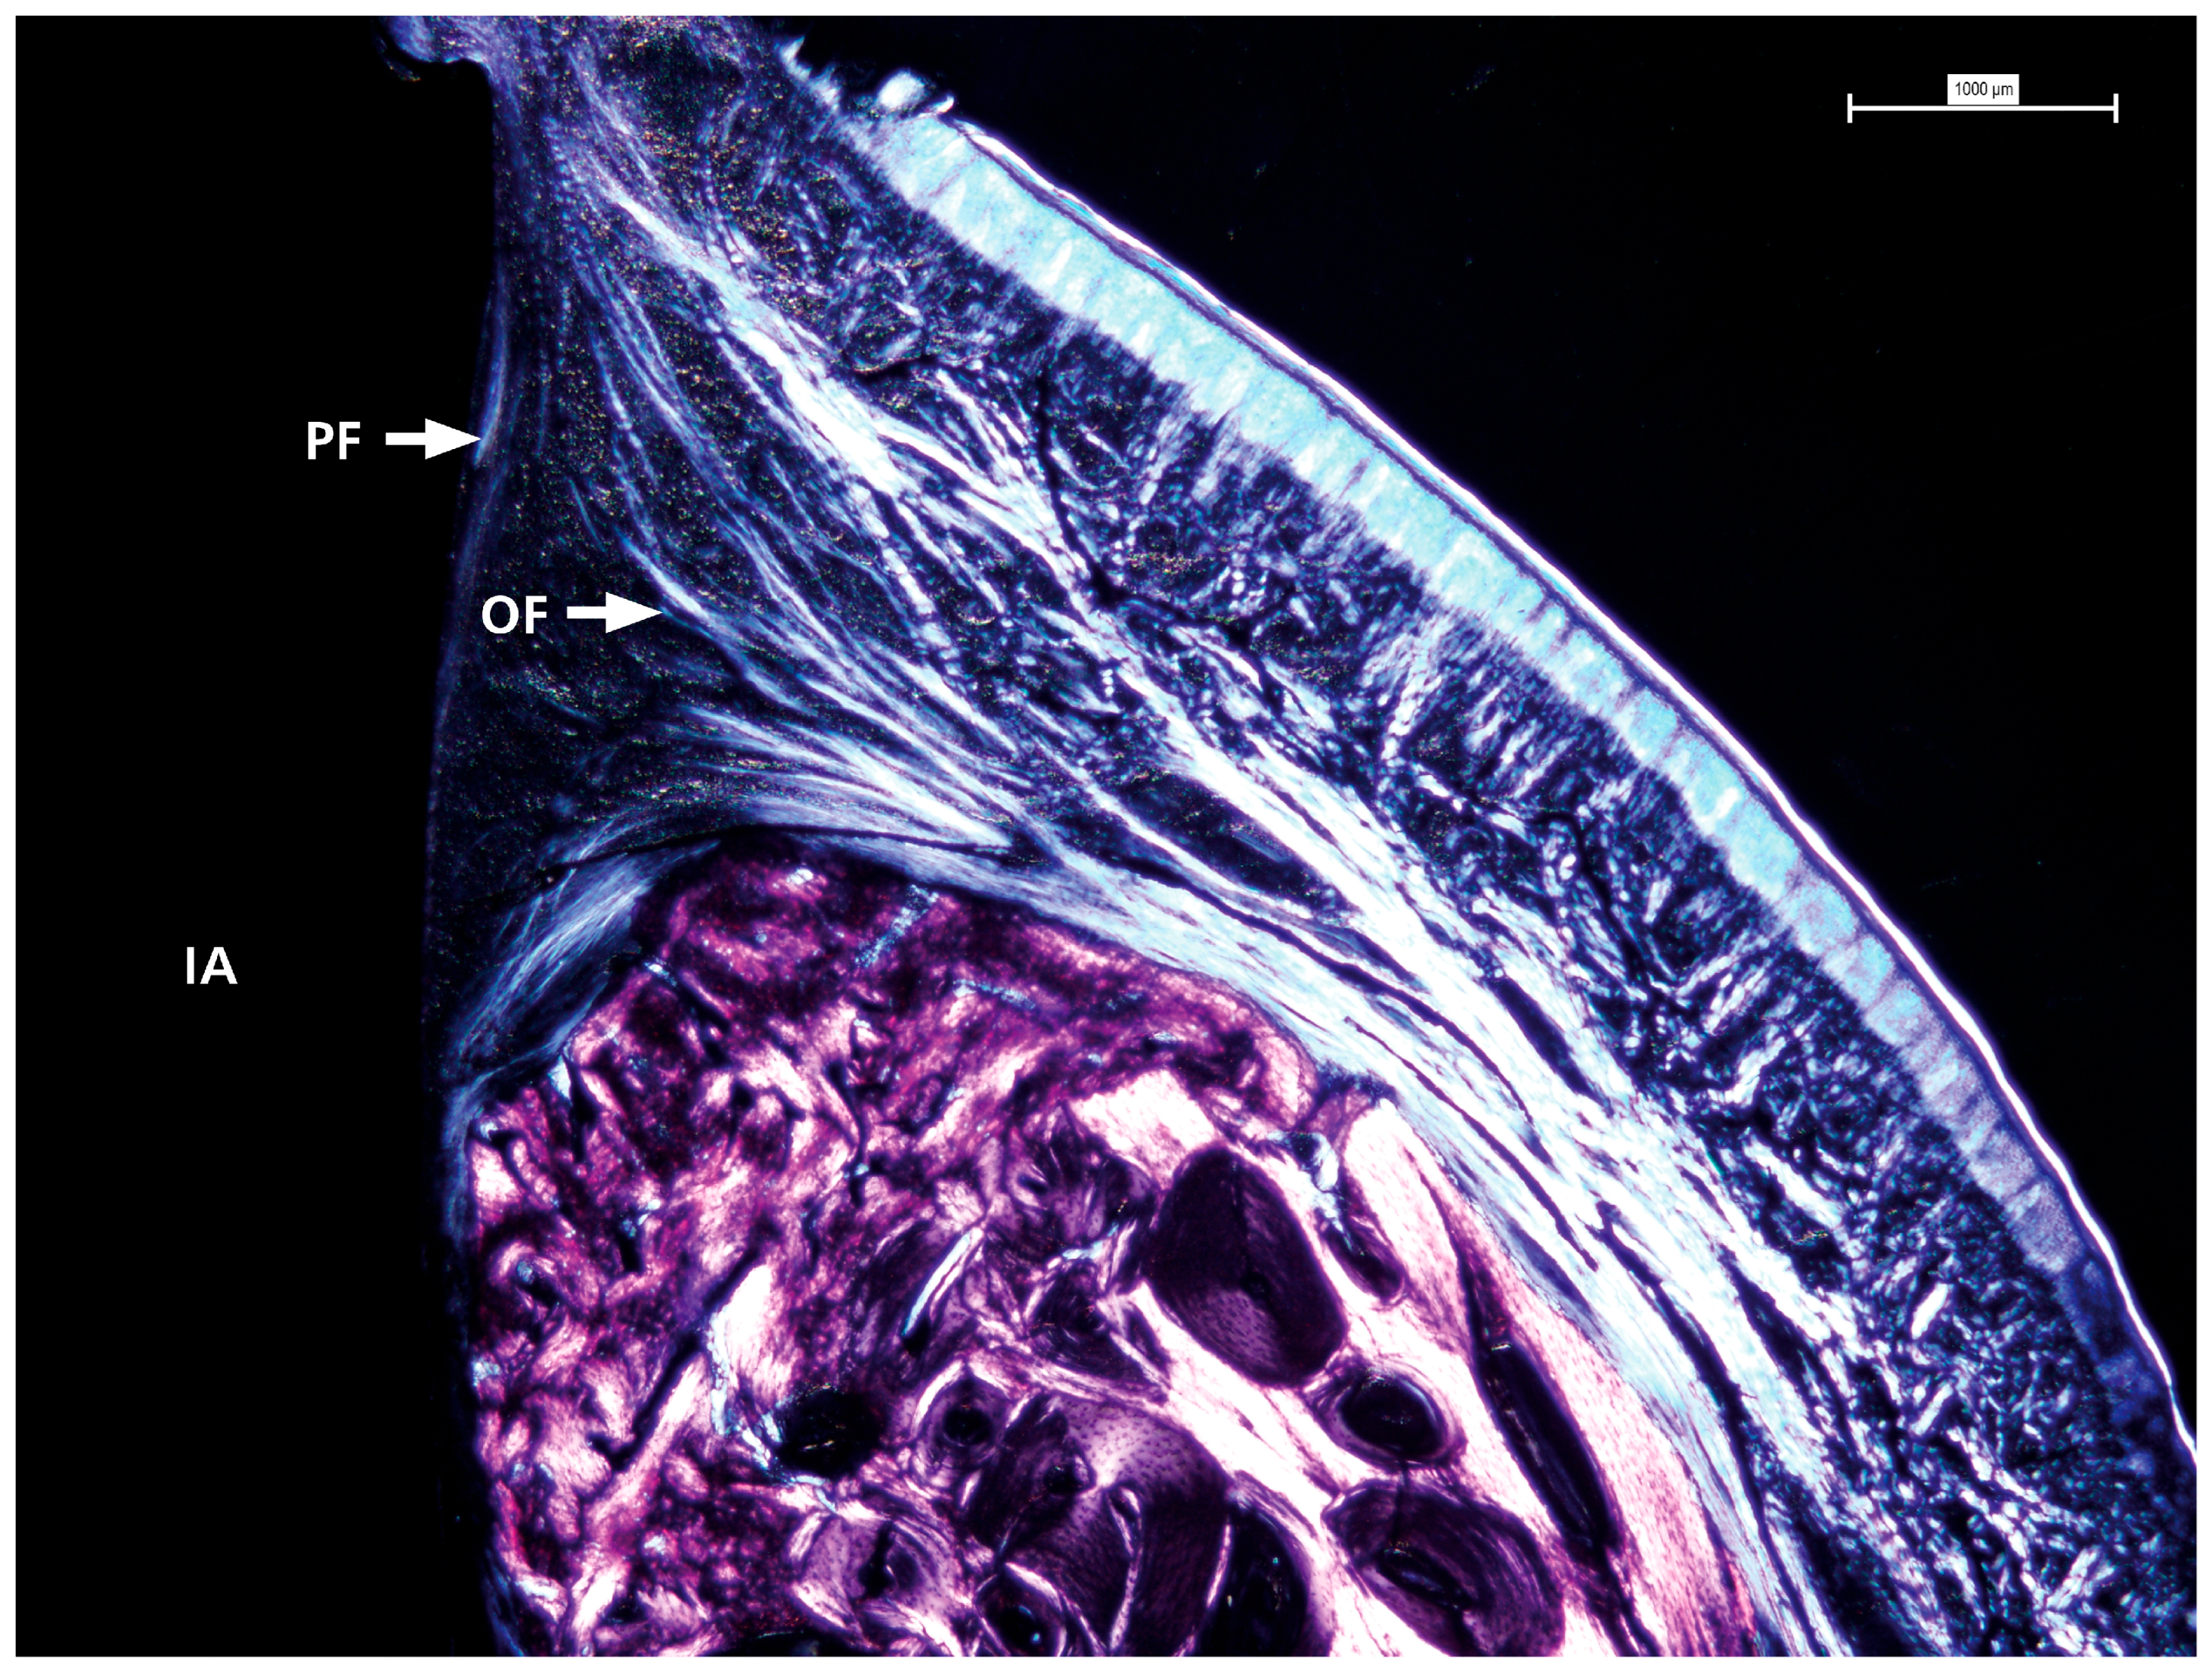

2.7. Polarized Images

3.3. Polarized Light